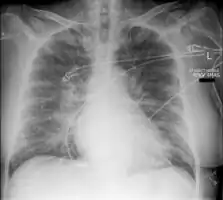

Acute pulmonary edema

Low oxygen saturation and disturbed arterial blood gas readings support the proposed diagnosis by suggesting a pulmonary shunt. A chest X-ray will show fluid in the alveolar walls, Kerley B lines, increased vascular shadowing in a classical batwing peri-hilum pattern, upper lobe diversion (increased blood flow to the superior parts of the lung), and possibly pleural effusions. In contrast, patchy alveolar infiltrates are more typically associated with noncardiogenic edema[8]